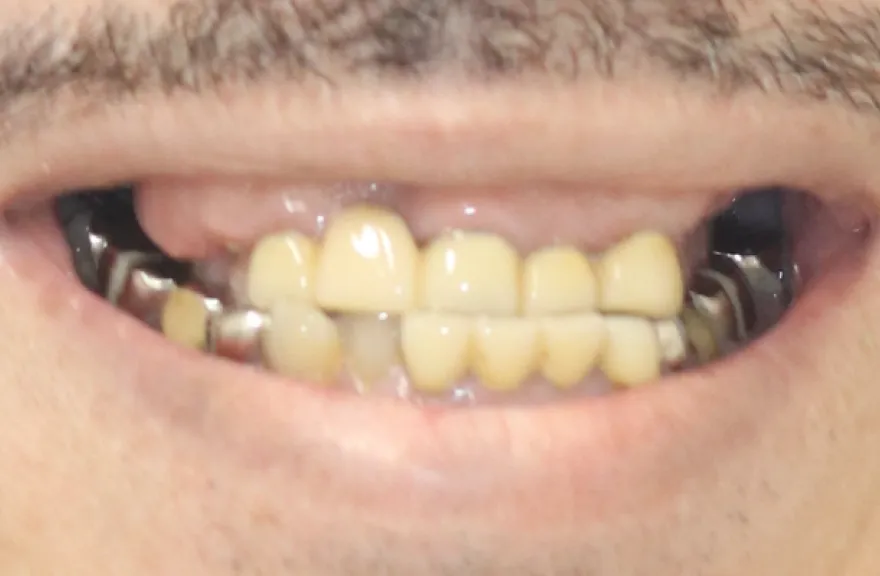

前歯を綺麗にしたい

- 相談内容

- 前歯を綺麗にしたい

- 患者情報

- 40代男性

- 来院時悩み

- 特になし

- 治療前の状態

- 空隙歯列(すきっぱ)、歯牙形態の不整

- 治療内容

- ホワイトニング・ラミネートベニア

- 治療期間

- 4ヶ月

- 治療費用

- オフィスホワイトニング ラミネートベニア 4本

【治療のリスク・注意点】

定期検診で噛み合わせをチェックする必要があり、調整を行うこともあります。噛み合わせの調整に費用はかかりません。メンテナンスが甘い場合、セラミックが欠けたり破損したりすることがあります。

ホワイトニングはほとんどの方が歯を白く明るく変化させることができますが、ごく稀にあまり変化が見られない場合もあります。この方は問題ありませんでした。